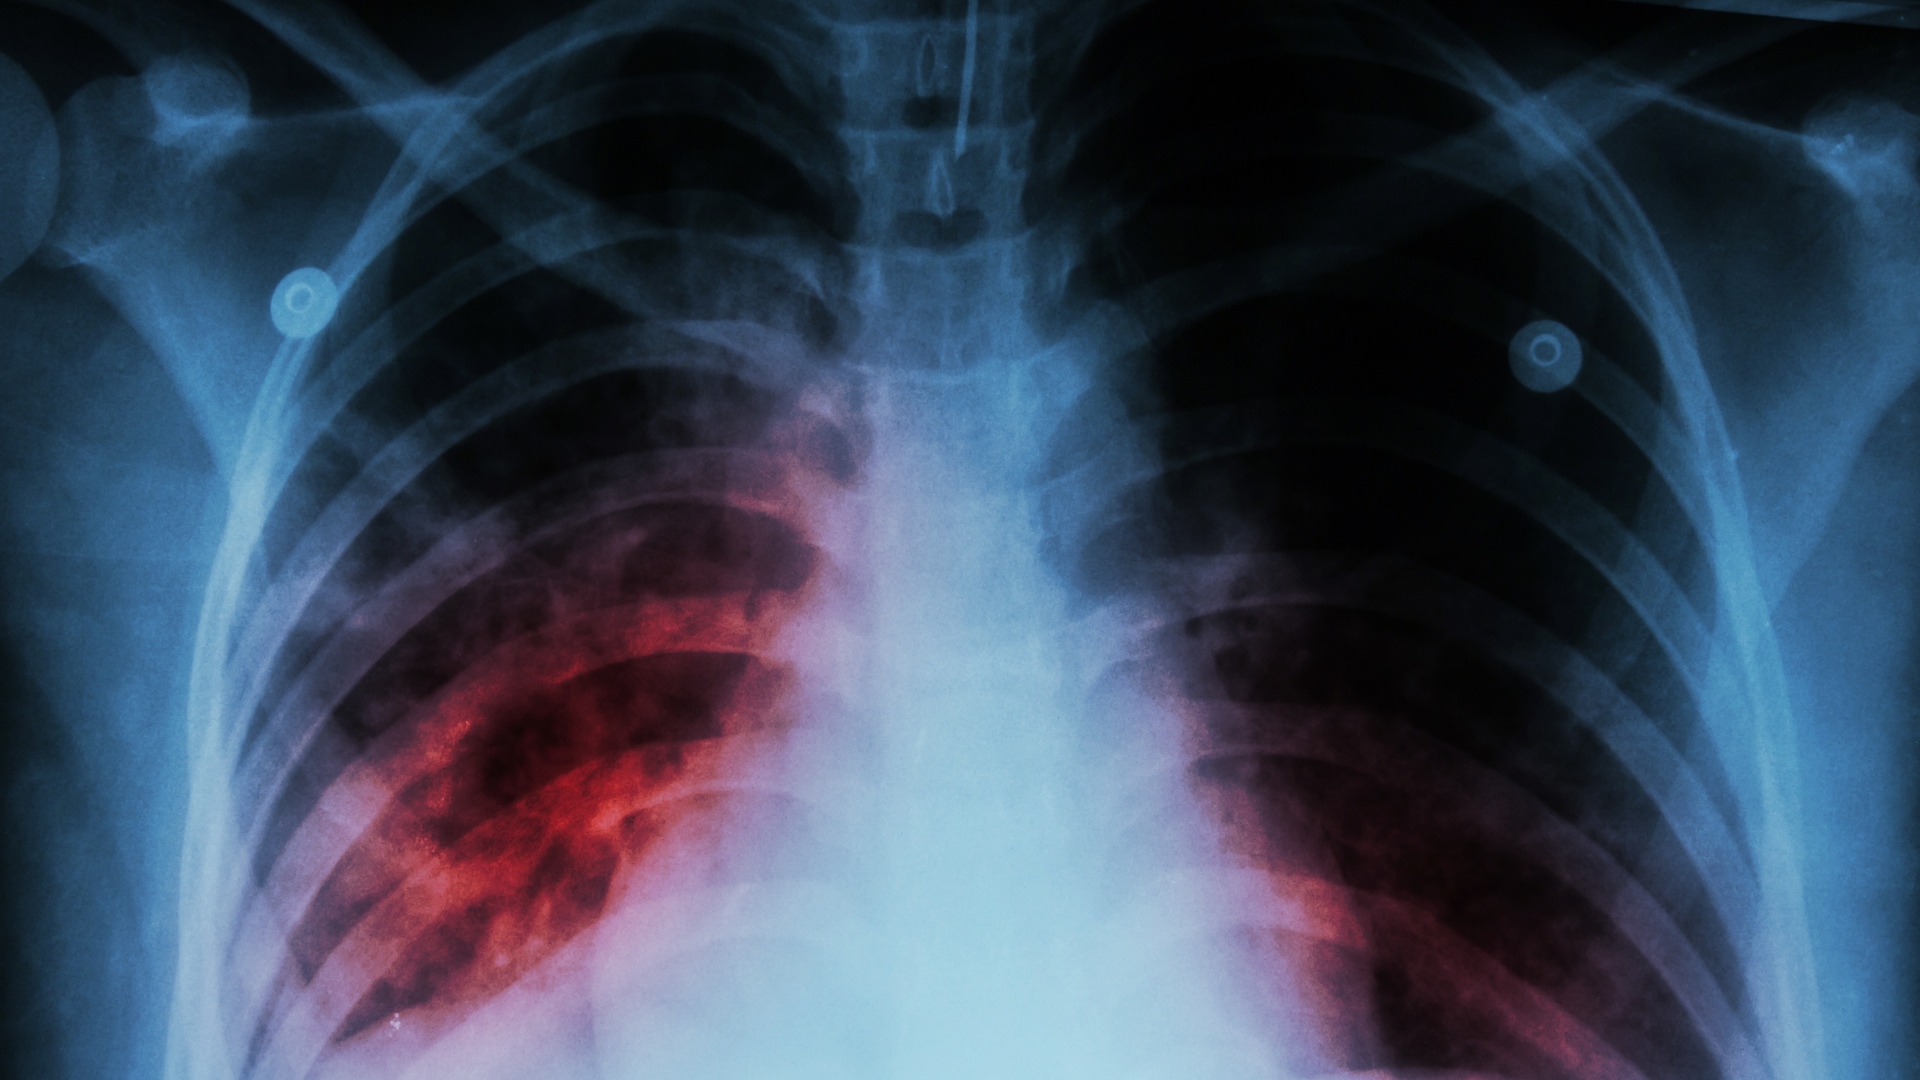

According to the World Health Organization (WHO), TB has been the leading cause of death worldwide from a single infectious agent (the microbe Mycobacterium tuberculosis) for most of the past decade (COVID-19 surpassed it in 2020). TB is responsible for some 1.5 million fatalities annually and greater than 30 million since 2000.